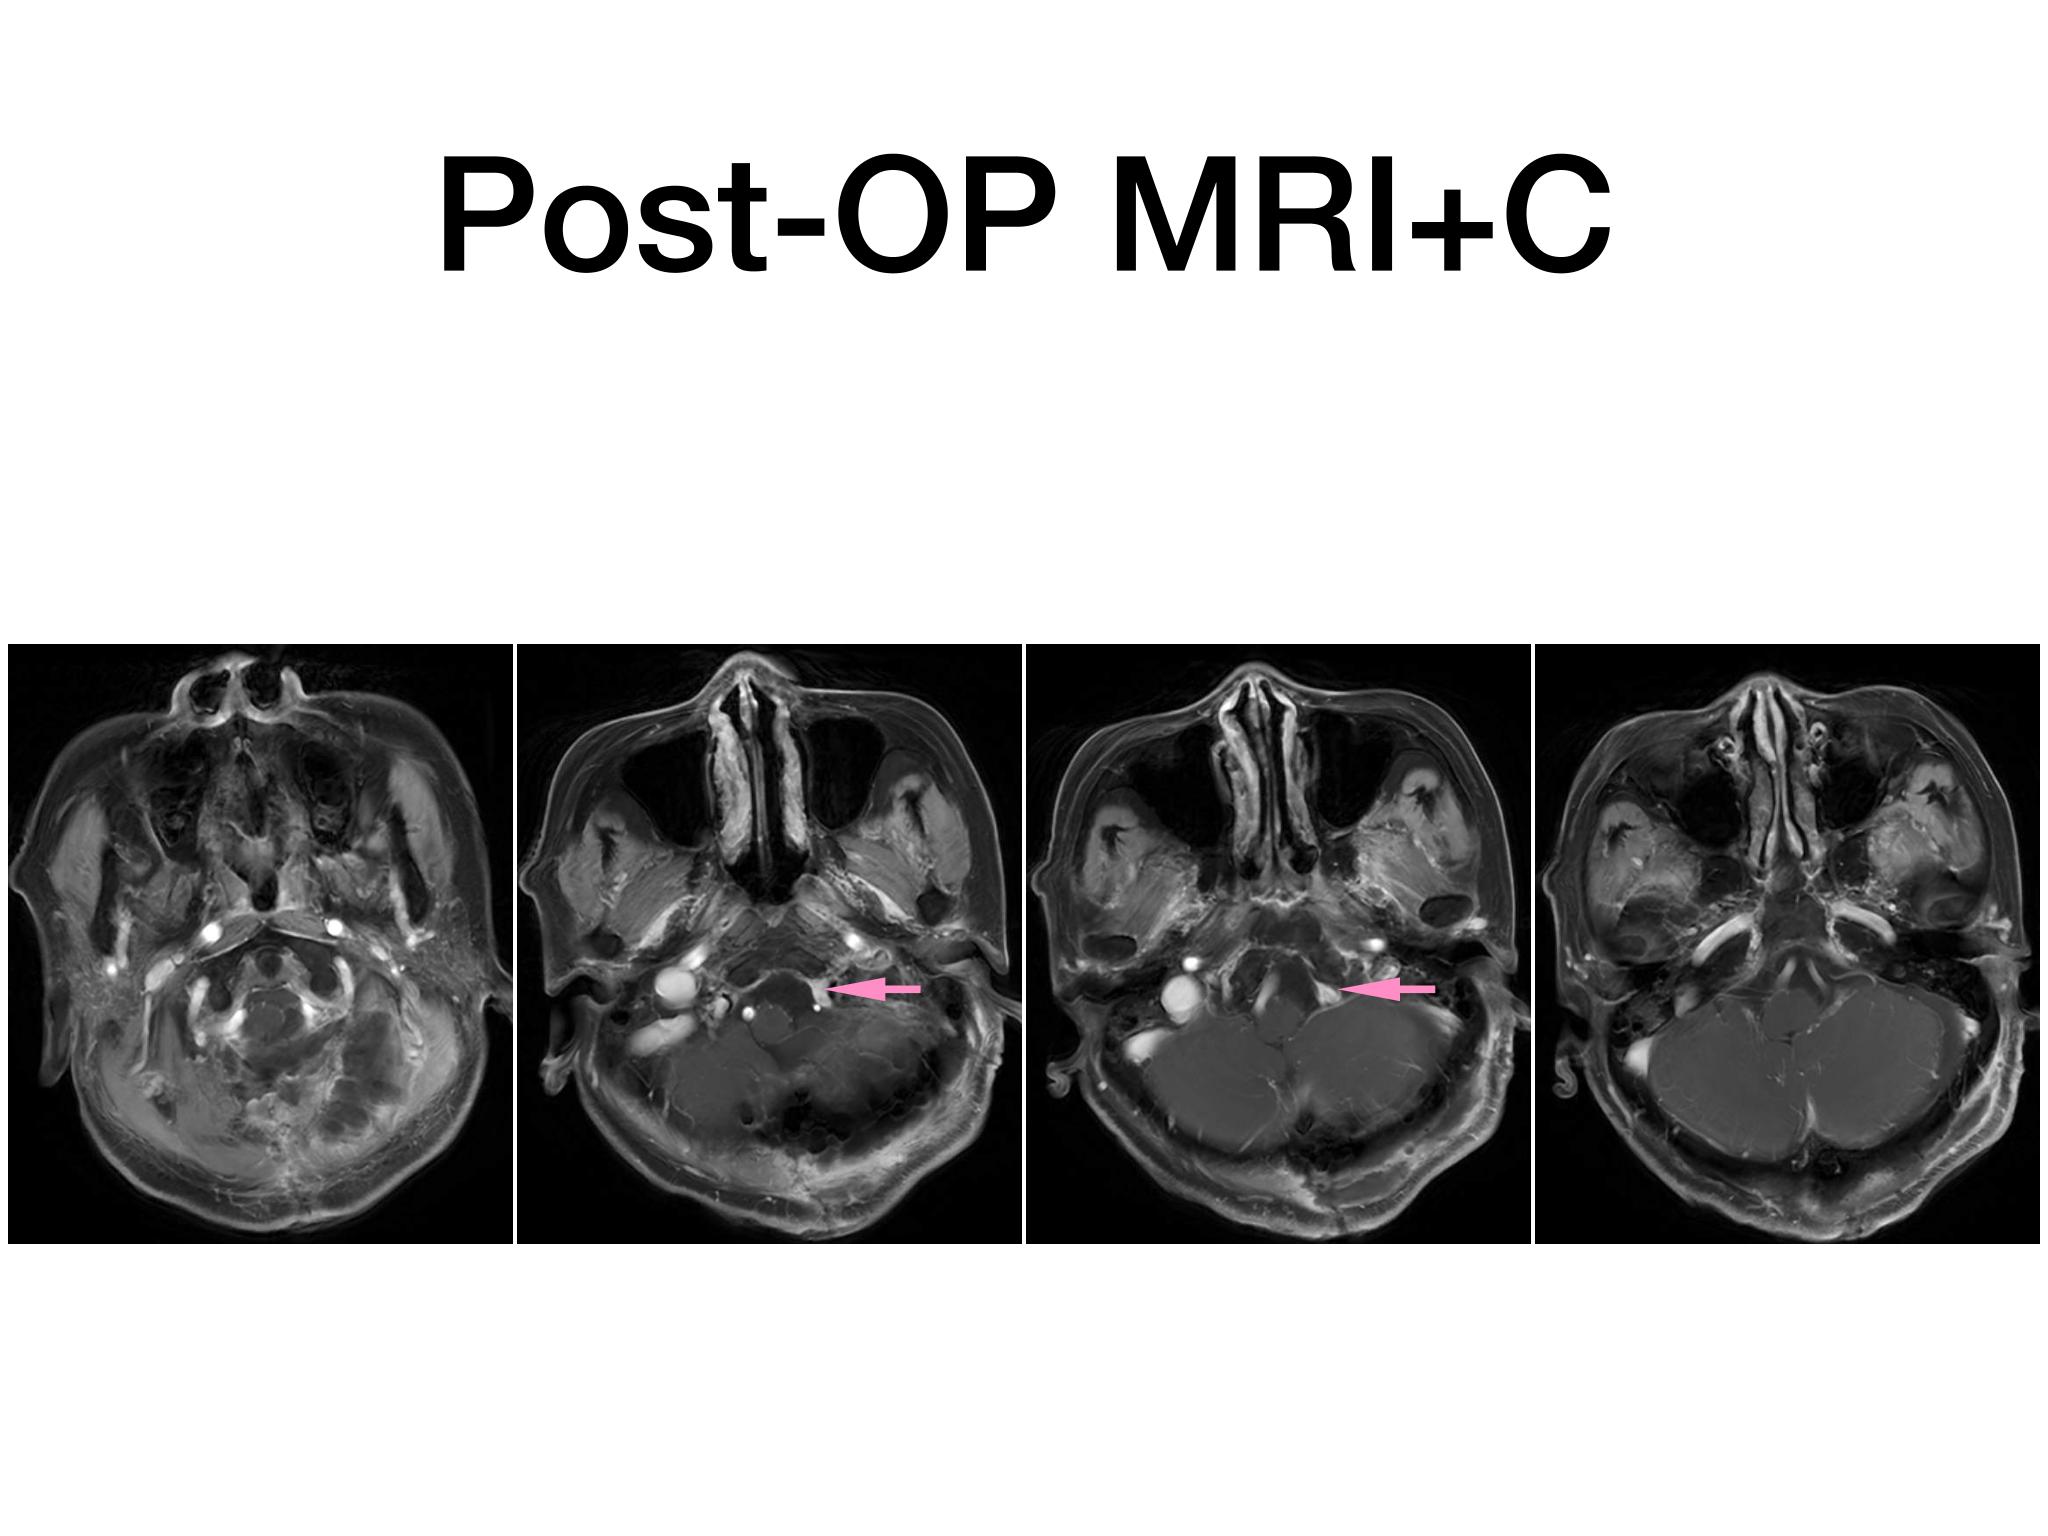

汇报一例后颅底肿瘤手术。为枕骨大孔巨大腹侧型脑膜瘤,该患者高龄,同时合并肺Ca,术前2周急性加重,枕骨大孔疝前期表现,术前已有延髓压迫及后组颅神经麻痹表现。经详细评估后采用远外侧经髁窝入路,最大化显露,重点保护延髓、后组颅神经,尽可能“零骚扰”。术中肿瘤质地韧,血供一般,与肿瘤上极与后组颅神经黏连紧密,最终99%切除,残留约1%,术后顺利康复出院,无新发症状,为后续进行肺部病变化疗创造有利条件。